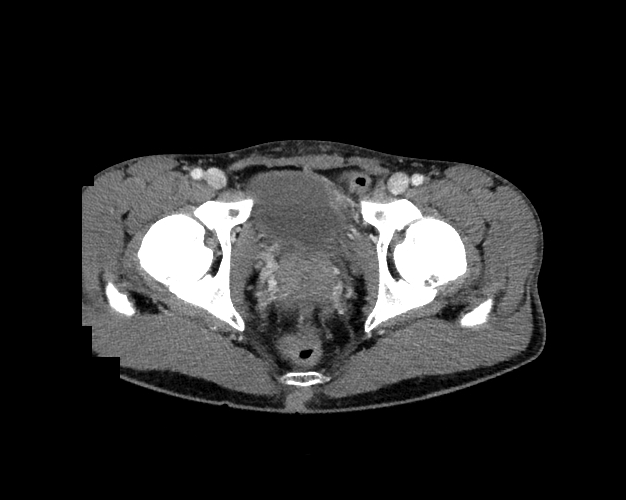

Pelvis

Covers pelvic MRI anatomy.